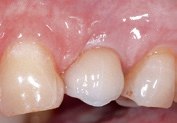

Patientenfall (Abb. 1 bis 8)

Aufgrund einer fortgeschrittenen parodontalen Erkrankung und eines schweren Knochenverlustes rund um den infizierten Zahn, musste der obere Prämolar des Patienten extrahiert werden. Im posterioren Oberkiefer wurde ein intraalveolärer Knochendefekt der Klasse I diagnostiziert, ohne eine Dehiszenz oder einen Fenestrationsdefekt vorzuweisen.

Dieser Patient wurde bereits im Jahr 1991 behandelt. Der Fall zeigt eine der ersten klinischen Anwendungen von Geistlich Bio-Oss Collagen. Aufgrund des intraalveolären Knochendefekts wurde eine Frühimplantation mit gleichzeitiger Augmentation durchgeführt. Die Implantation wurde 6 Wochen nach Extraktion des Prämolars vorgenommen. In der postoperativen Phase erfolgte eine unauffällige Weichgewebeheilung nach Extraktion. Für die Implantatinsertion wurde der Frühimplantationsansatz mit einer Heilungsphase von 6 Wochen gewählt. Die Knochenaugmentation wurde gleichzeitig mit der Implantatinsertion durchgeführt. Das Implantat wurde nach der Lappenpräparation an einer Stelle mit einem schweren Knochendefekt eingesetzt.

Für den Knochenaufbau wurde Geistlich Bio-Oss Collagen in den Defekt appliziert und nach der Augmentation die Eingriffsstelle mit einem Kollagenvlies abgedeckt. Weitere 6 Monate nach dem Eingriff wurde die endgültige Kronenrestauration eingesetzt. Bei der weiteren Nachuntersuchung nach nunmehr 25 Jahren zeigte die Röntgenaufnahme ein stabiles Implantatlager und das klinische Bild bei der Nachkontrolle einen ästhetischen Zahnstatus.